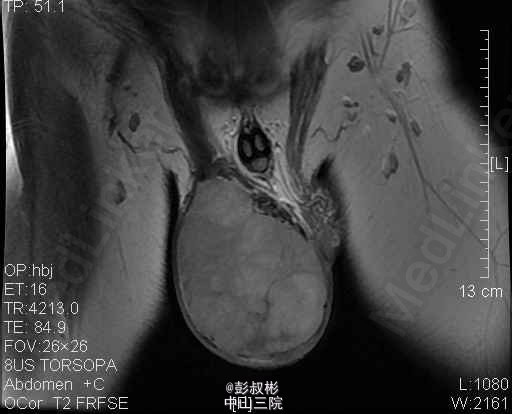

1、主诉:发现右侧睾丸肿大1年。 2、患者为青年男性,隐匿性起病。患者于一年前无明显诱因发现右侧睾丸变硬,并逐渐增大,无疼痛与牵引感,也不影响排尿和日常活动,未经任何诊治,近来自觉右侧睾丸钝痛,到我院门诊求诊,诊断为:"右侧睾丸肿瘤"。现为进一步诊治收入我科。起病以来,患者无寒战、发热,无恶心、呕吐、腹泻,食欲、精神、睡眠一般,大便正常,近期体重无明显下降。。 3、体格检查:双肾区无红肿、隆起,无叩痛,双侧肋脊点、肋腰点无压痛。腹平软,双侧输尿管走行区无压痛,膀胱区无膨隆,压痛阴性,双侧腹股沟区未触及肿物,阴毛呈男性分布,外生殖器发育正常,尿道外口未见异常,右侧阴囊内可触及右侧睾丸明显增大,约“20×10×8”cm大小,轻压痛,透光试验(-)。直肠指检:胸膝位,前列腺不大,质韧,中央沟存在,表面光滑,无结节,触痛阴性,指套未见沾血。 4、辅助检查:B超示:右侧睾丸肿瘤。盆腔MR平扫+增强扫描提示:右侧阴囊内占位,考虑睾丸来源恶性肿瘤,精原细胞瘤可能大。 5、诊疗措施:入院后予患者完善相关检查,三大常规及生化回报未见明显异常,未见明显手术禁忌症,考虑患者可耐受手术,拟予患者行右侧睾丸治疗根治性切除术。